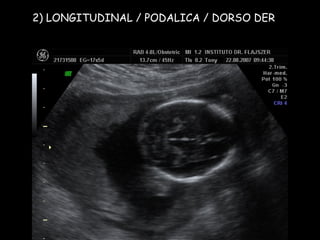

2) LONGITUDINAL / PODALICA / DORSO DER

Apex y estómago: ¿Cerca o lejos del transductor? Long/Pod/D.der Lejos